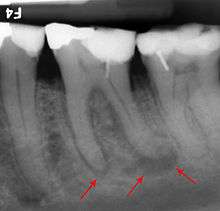

The periodontal ligament becomes inflamed and there may be pain when biting or tapping on the tooth. On an X-ray, bone resporption appears as a radiolucent area around the end of the root, although this does not manifest immediately.[9]:228 Acute apical periodontitis is characterized by well-localized, spontaneous, persistent, moderate to severe pain.[4]:125–135 The alveolar process may be tender to palpation over the roots. The tooth may be raised in the socket and feel more prominent than the adjacent teeth.[4]:125–135

- Radiographs utilized to find dental caries and bone loss laterally or at the apex.